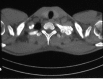

Figure 2.

Non-contrast enhancement CT demonstrates an oval sclerotic, expansile lesion with spongy-form speckled calcification and a well-demarcated lesion involving the posterolateral side of the left first rib.